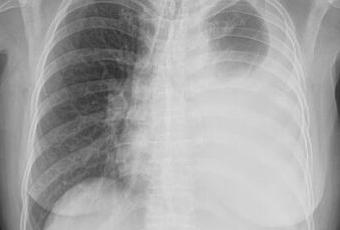

PA DE TORAX (TELE DE TORAX)

LA PROYECCION RADIOLOGICA OBTENIDA NOS MUESTRA LOS SIGUIENTES HALLAZGOS:

-Tejidos blandos, con densidad conservada, simétricos, sin evidencia de alteraciones.

-Estructuras óseas, sin evidencia de lesiones líticas, blásticas o perdida de la contigüidad.

-Vía aérea permeable, con desplazamiento de la tráquea hacia derecha.

-Mediastino, con desplazamiento hacia derecha

-Corazón, no se prueba de manera adecuada.

-Hilios pulmonares, derechos sin alteraciones, izquierdo no se puede valorar por opacidad en pulmón izquierdo.

-Trama bronco-vascular, en lo observado de trayecto y calibre adecuado.

-Campos pulmonares, derecho sin evidencia de opacidades, nódulos o masas. Pulmón izquierdo, con radioopacidad en segmentos inferiores, de un 70% aproximadamente, con efecto de masa desplazando mediastino hacia lado derecho.

-Receso costofrénico y cardiofrénico izquierdos ocupados. Resto de Recesos cardiofrénicos y costofrénico sin alteraciones.

OPINIÓN RADIOLÓGICA:

EN EL PRESENTE ESTUDIO RADIOGRÁFICO, CAVIDAD TORÁCICA IZQUIERDA, CON DERRAME PLEURAL 70% APROXIMADAMENTE VS ORIGEN A DETERMINAR.